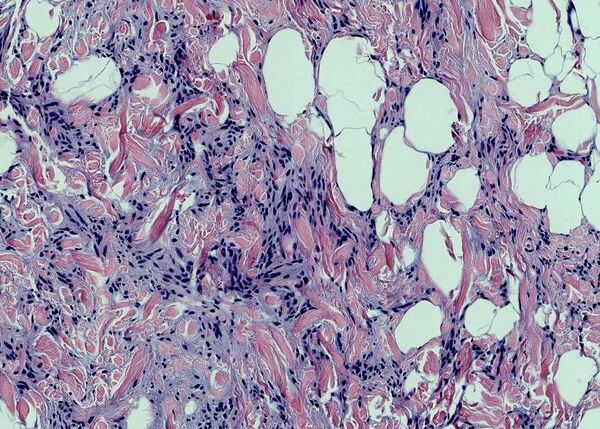

Клетки жировой ткани, накапливающие жир, называют адипоцитами. Одиночные адипоциты имеют шарообразную форму. Жировую ткань принято подразделять на белую и бурую согласно её цвету. Адипоцит белой жировой ткани содержит одну большую каплю нейтрального жира (такие адипоциты также называют унилокулярными), которая занимает центральную часть клетки и окружена тонким слоем цитоплазмы, в утолщённой части которого залегает уплощённое ядро. В цитоплазме адипоцитов содержатся в небольших количествах и другие липиды: холестерин, фосфолипиды, а также свободные жирные кислоты. Эти мелкие жировые включения особенно выражены у незрелых адипоцитов. Зрелый адипоцит имеет крупные размеры, от 50 до 150 мкм. Так как липиды вымываются ксилолом и другими растворителями, использующимися при приготовлении гистологических препаратов, унилокулярные адипоциты при рассмотрении с помощью светового микроскопа выглядят пустыми[1].